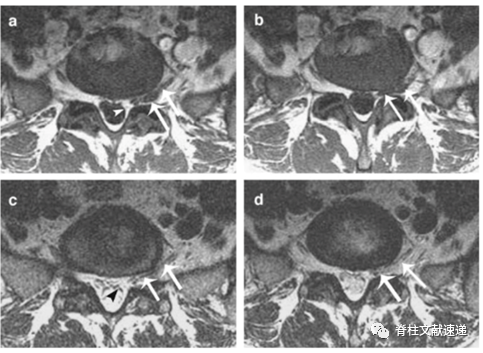

术中已经证实异常神经根。三角所示为角形征,双箭头所示为平行征(即异常神经根影)。

术中已经证实异常神经根。三角所示为新月形脂肪。

三角所示为角形征,箭头所示为新月形脂肪。

箭头所示为角形征,弯箭头所示为新月形脂肪,双三角所示为平行征(即异常神经根影)。